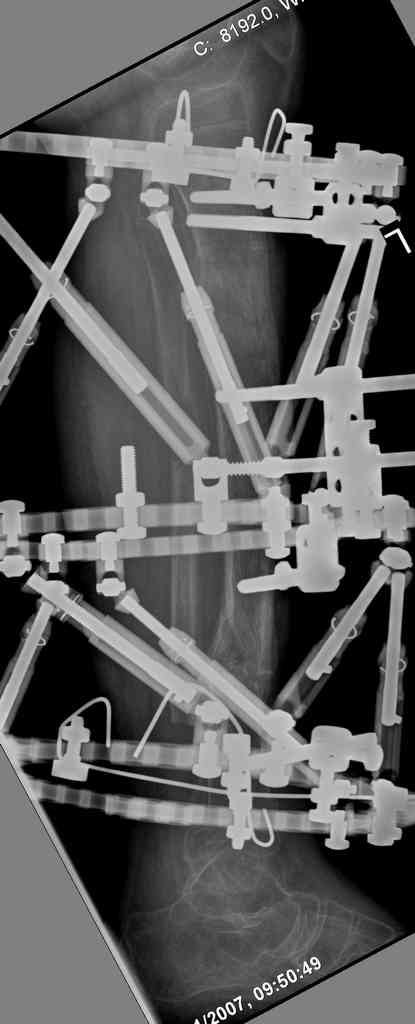

Another choice is simply perform shortening + posterior angulation with Ilizarov or TSF , than gradual correction of the angulation.After all apply third ring on the proximal tibia and start lengthening.

We had recently similar case in 14 years old boy with 45 mm bone defect after open tibial fracture.Boy doing excellent .This technique is not new, Sasha Lerner did it in Rambam , Rozbruch wrote also.

Another advantage of this techniqe is relaxation of soft tissue and possibility for closure even large defects of the skin.In your case I will apply ring on the foot and mid diaphysis of the tibia ,removal of the fibular plate,sindesmotic wire, and after correction of angulation on the proximal tibia.

Действительно, если есть длинная косая линия на проксимальном отломке, это жалко будет не использовать. Можно сделать коррекцию угла не обратным разведением фрагментов, а оставить их в контакте, и сделать кортикотомию проксимальнее на 2-3 см. Можно и сейчас отсечь такой фрагмент и транспортировать его с разворотом. Наверно, вариант с ангуляцией более технологичен.

Да, надо удалить все железо, сделать для ангуляции остеотомию малоберцовой на уровне дефеормации, а после восстановления оси сразу освободить стопу. То есть в дистальном отломке tibia надо побольше

спиц с упорами, а на диафизе только half-pins с передне-внутренней стороны, чтобы как можно меньше пострадала передняя группа мышц.